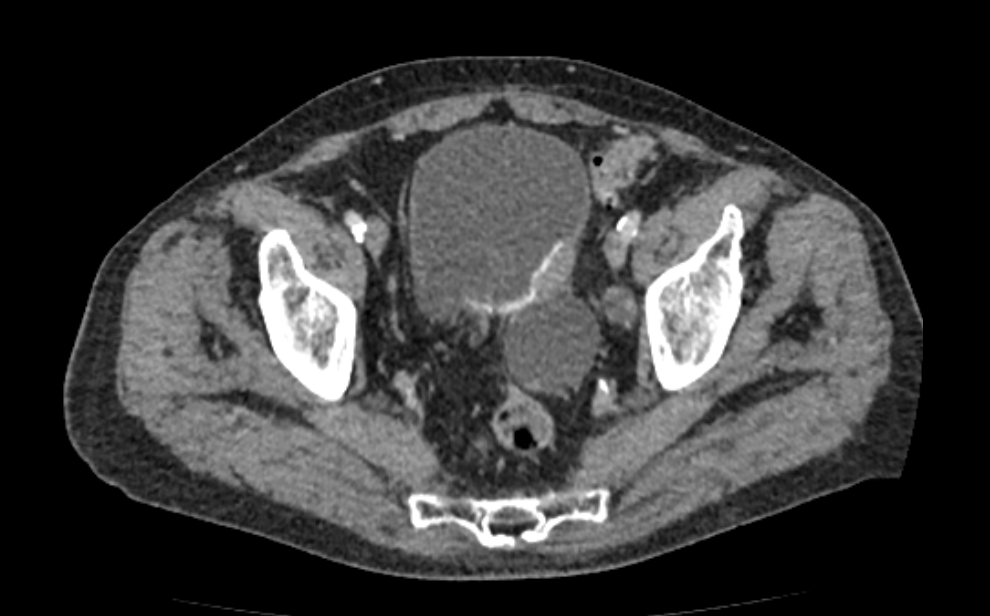

- Новообразования злокачественные и доброкачественные (в случае опухолей КТ с контрастом позволяет выявить ранее заподозренную опухоль, оценить прогрессию роста опухоли, оценить результаты лечения опухолей: химиотерапии или хирургического вмешательства).

Также стоит отметить, что на КТ с применением контрастного вещества достаточно отчетливо и достоверно можно дифференцировать метастазы в соседних органах.